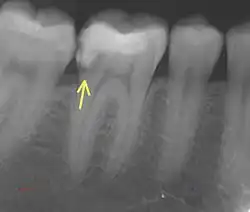

a. Periapical Radiographs

These provide detailed 2D images of the tooth and can detect fractures extending into dentin but may miss subtle enamel-only cracks due to their limited resolution.

b. CBCT

CBCT offers 3D imaging with high spatial accuracy, ideal for locating and assessing fractures extending into dentin or adjacent structures.